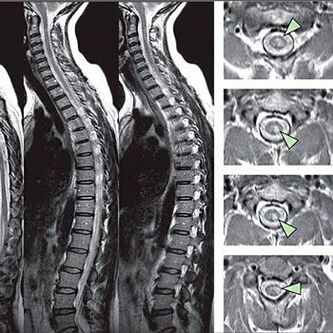

Методи за диагностициране на остеохондроза на гръдния стълб

За да се идентифицират признаци на нарушения на чувствителността, се извършват специални функционални тестове. Най -информативната опция за диагностика от инструментални методи е ефективността на x -ray. Въпреки това, за задълбочено проучване на гръбначния стълб често се провеждат ЯМР и КТ. В случай на подозрение за заболявания на сърдечно -съдовата система, пациентът се препоръчва да претърпи процедурата на ЕКГ.